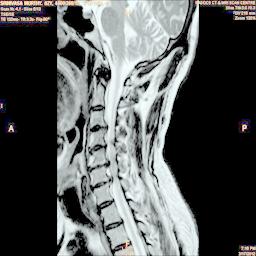

The proposed algorithm uses HSV color space to enhance spinal cord images since this color space offers many advantages such as color separation from intensity, reduced color distortion and efficient enhancement. The algorithm proposed takes advantage of this color space by performing enhancment operation on the intensity or value component and preserving the color information. The first column of Fig. 3 shows the original spinal cord test images followed by the extraction of value component presented in second column. Next, the third column of Fig. 3 shows the value component enhanced using the proposed multirate multiscale retinex algorithm. The modified version of the retinex algorithm presented here is capable of producing high quality reconstructed pictures, far better than the other researchers method.

The developed algorithm presented in the previous section was coded using Matlab Version 8.0. The experiment was conducted by considering poor quality spinal cord images of having various lesions. The first column of Fig. 4 shows the axial view of neck spinal cord images of size pixels, respectively. The second column of Fig. 4 presents the same images enhanced using histogram equalization. As is evident from the results presented, the histogram equalization method performs global image enhancement operation which improves the contrast of an image but at the cost loss in image details. The third column of Fig. 4 shows the MSR based spinal cord image enhancement. It can be seen that from the result presented, MSR scheme improves the details that are not clearly visible in histogram equalization technique. In general, image enhancement achieved by MSR method is better compared to histogram equalization. However, the MSR method voilates gray world assumption. Therefore, the image enhanced by this scheme appears to be grayish. Although, numerous work have been reported for solving the problem due to gray world voilation, no work seems to developed for complete elimination.

The fourth column of Fig. 4 shows the image enhanced using Chao et al. []. It can be seen from the results presented that the reconstructed images of Chao’s method have black spots. The appearance of these dark patches degrades the visual quality of the enhanced image. The image enhanced using proposed multirate multiscale retinex image enhancement method presented in the fifth column of Fig. 4, overcomes the drawback of the Chao’s method. As we can see from the simulation results, image enhancement achieved by the proposed method has improved details with significant contrast enhancement. The enhanced images from the proposed method provides information to physicians, radiologists and researchers for various types of pathology detection.